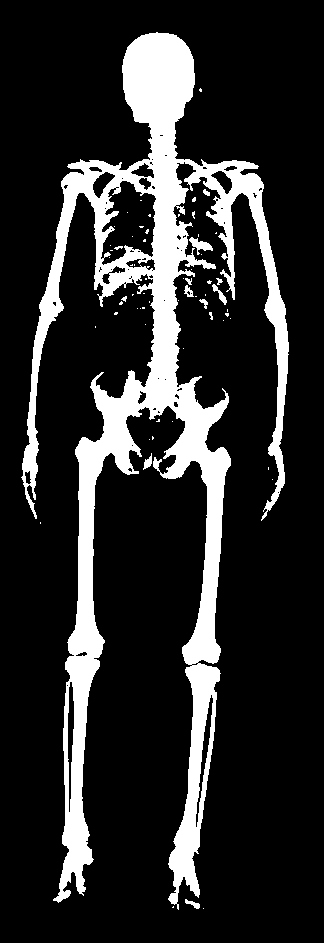

In this work, we address the problem of inferring the human anatomic skeleton, i.e. the bone shapes and locations, solely from surface observations. That is, we infer the bones from the skin. To that end, we learn a statistical model of the skeleton shape and its correlation with the skin surface (Fig. 1 left). Given a posed body, our method predicts the skeleton from the body shape, and poses it inside subject to anatomic constraints (Fig. 1 right).

5.4 Generalization to new poses